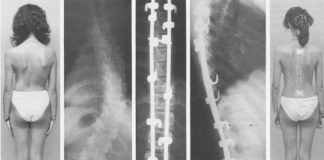

Эффективное лечение сколиоза